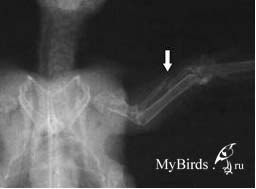

Пациент после операции: Интрамедуллярный остеосинтез сломанной лучевой кости с помощью внутрикостной спицы (ВК спица, стрелка: выход штифта). Photo: C. Haupt

Перелом лучевой кости после внутрикостной фиксации 0,4 мм канюлей |

Относительно частые переломы лучевой кости, которые при отсутствии лечения могут привести к ограниченной возможности полета, скрепляются с помощью 0,4 мм канюли, вставляемой в дистальный конец перелома. Канюля выходит через головку лучевой кости, определяемой пальпацией в плечевом суставе, и проталкивается в обратном направлении в проксимальный конец перелома до тех пор, пока не окажется прямо перед локтевым суставом. Спица, выходящая из плечевого сустава, должна на 1-2 мм выходить из кожи; конец спицы необходимо закрыть небольшим кусочком пластыря, чтобы пациент не смог ее вытянуть.